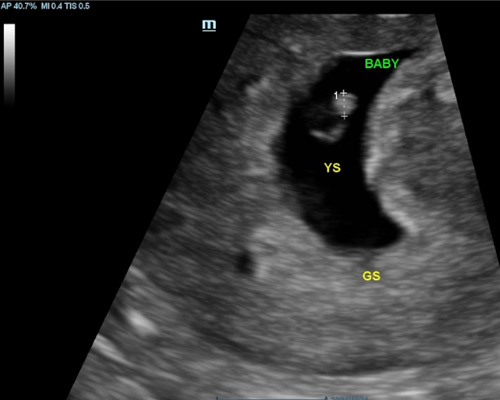

A viability scan is usually performed between 6 and 12 weeks to assess early development. It can help confirm the pregnancy, estimate dates, and check for key signs such as the gestational sac, fetal pole, and a heartbeat where visible. This scan is often chosen by those who want early clarity, have concerns, or simply wish for reassurance before their first routine appointment.

- Visual confirmation of the fetal heartbeat

- A 2D ultrasound to confirm an intrauterine pregnancy

Sometimes it may be needed to perform a Transvaginal (Internal) scan for clear imaging in addition to abdominal scan, this involves inserting a thin probe into the vagina. It is safe and your consent will be obtained beforehand.

The scan looks at early development, including location, measurements, and whether a heartbeat can be seen, depending on how far along you are.